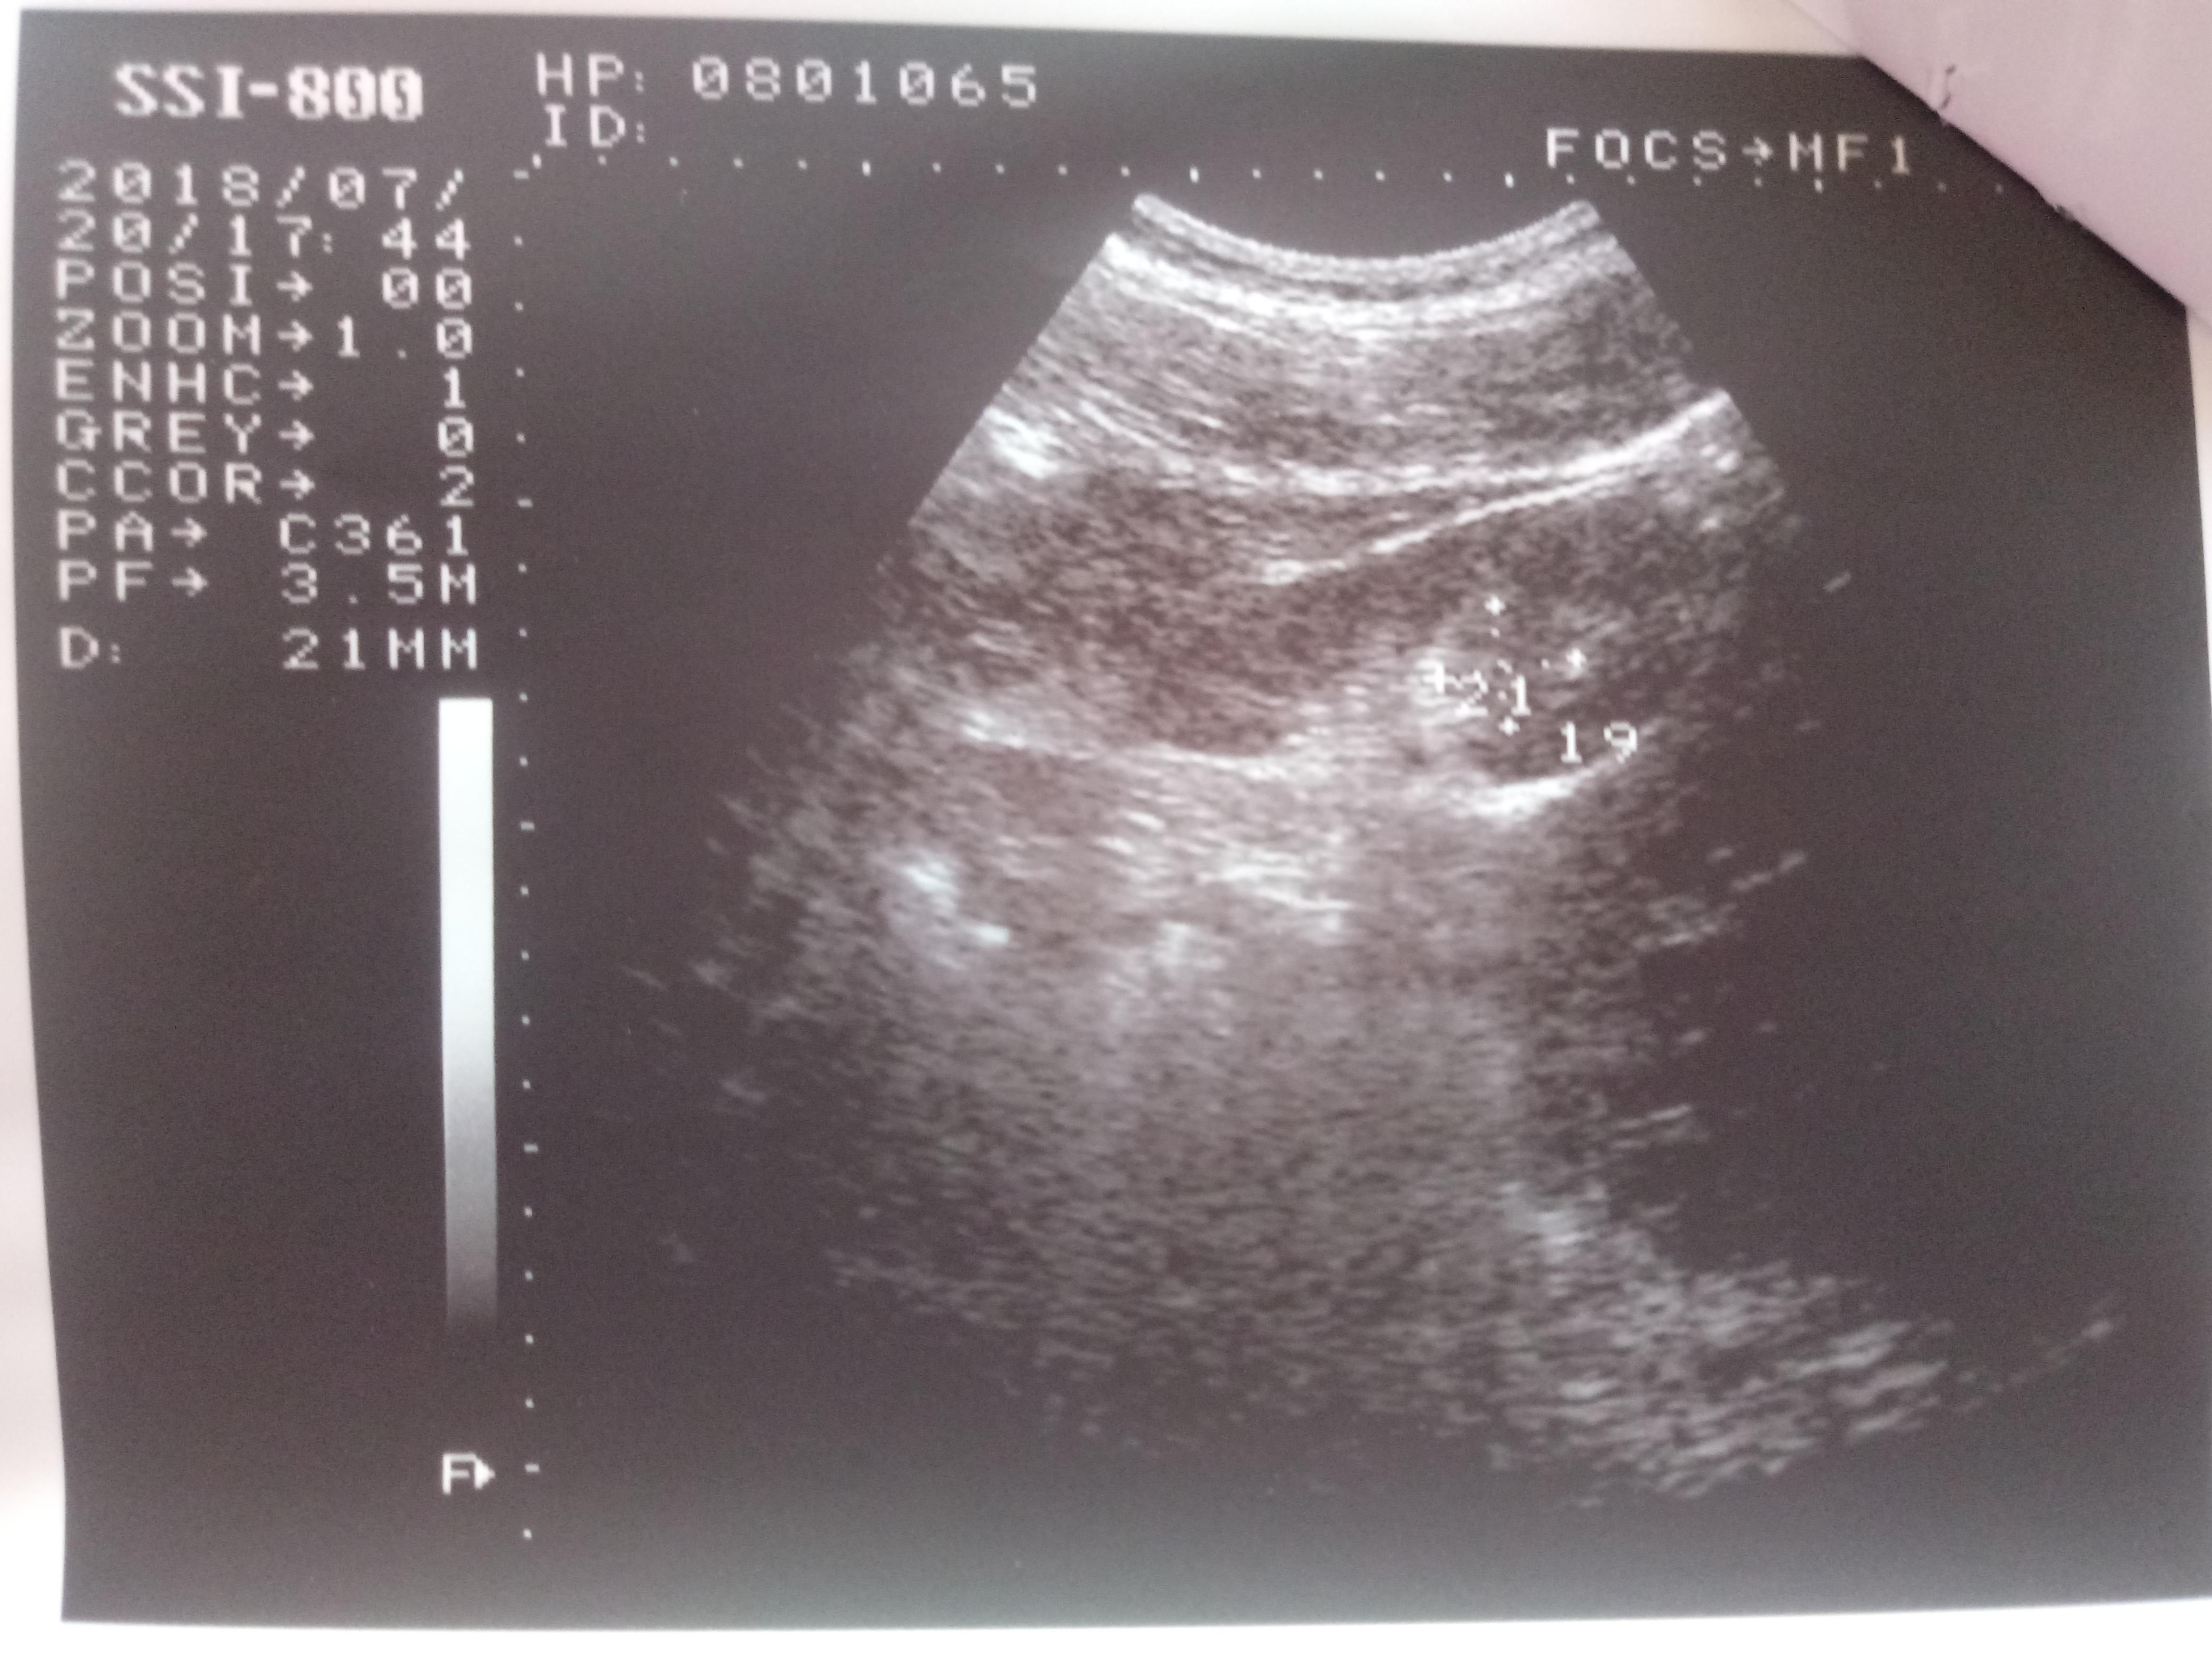

Добрый день! Моему сыну 15 лет. В его моче обнаружено большое количество эритроцитов. Узи почек показало "МКД обеих почек и киста правой почки". Назначение терапевта: уродан 1 ч/л×100 мл.×2 р.д. 30 дней,конефрон 1 таб×3 р.д. 30 дней. Скажите, пожалуйста, насколько это серъезно? Дело в том, что мой сын поступает в военную школу. Сами понимаете, там физические нагрузки. Можно ли нам там учиться с таким диагнозом? И какое лечение посоветуете? Нужно ли нам дополнительно сделать КТ или МРТ?

Ответ врача